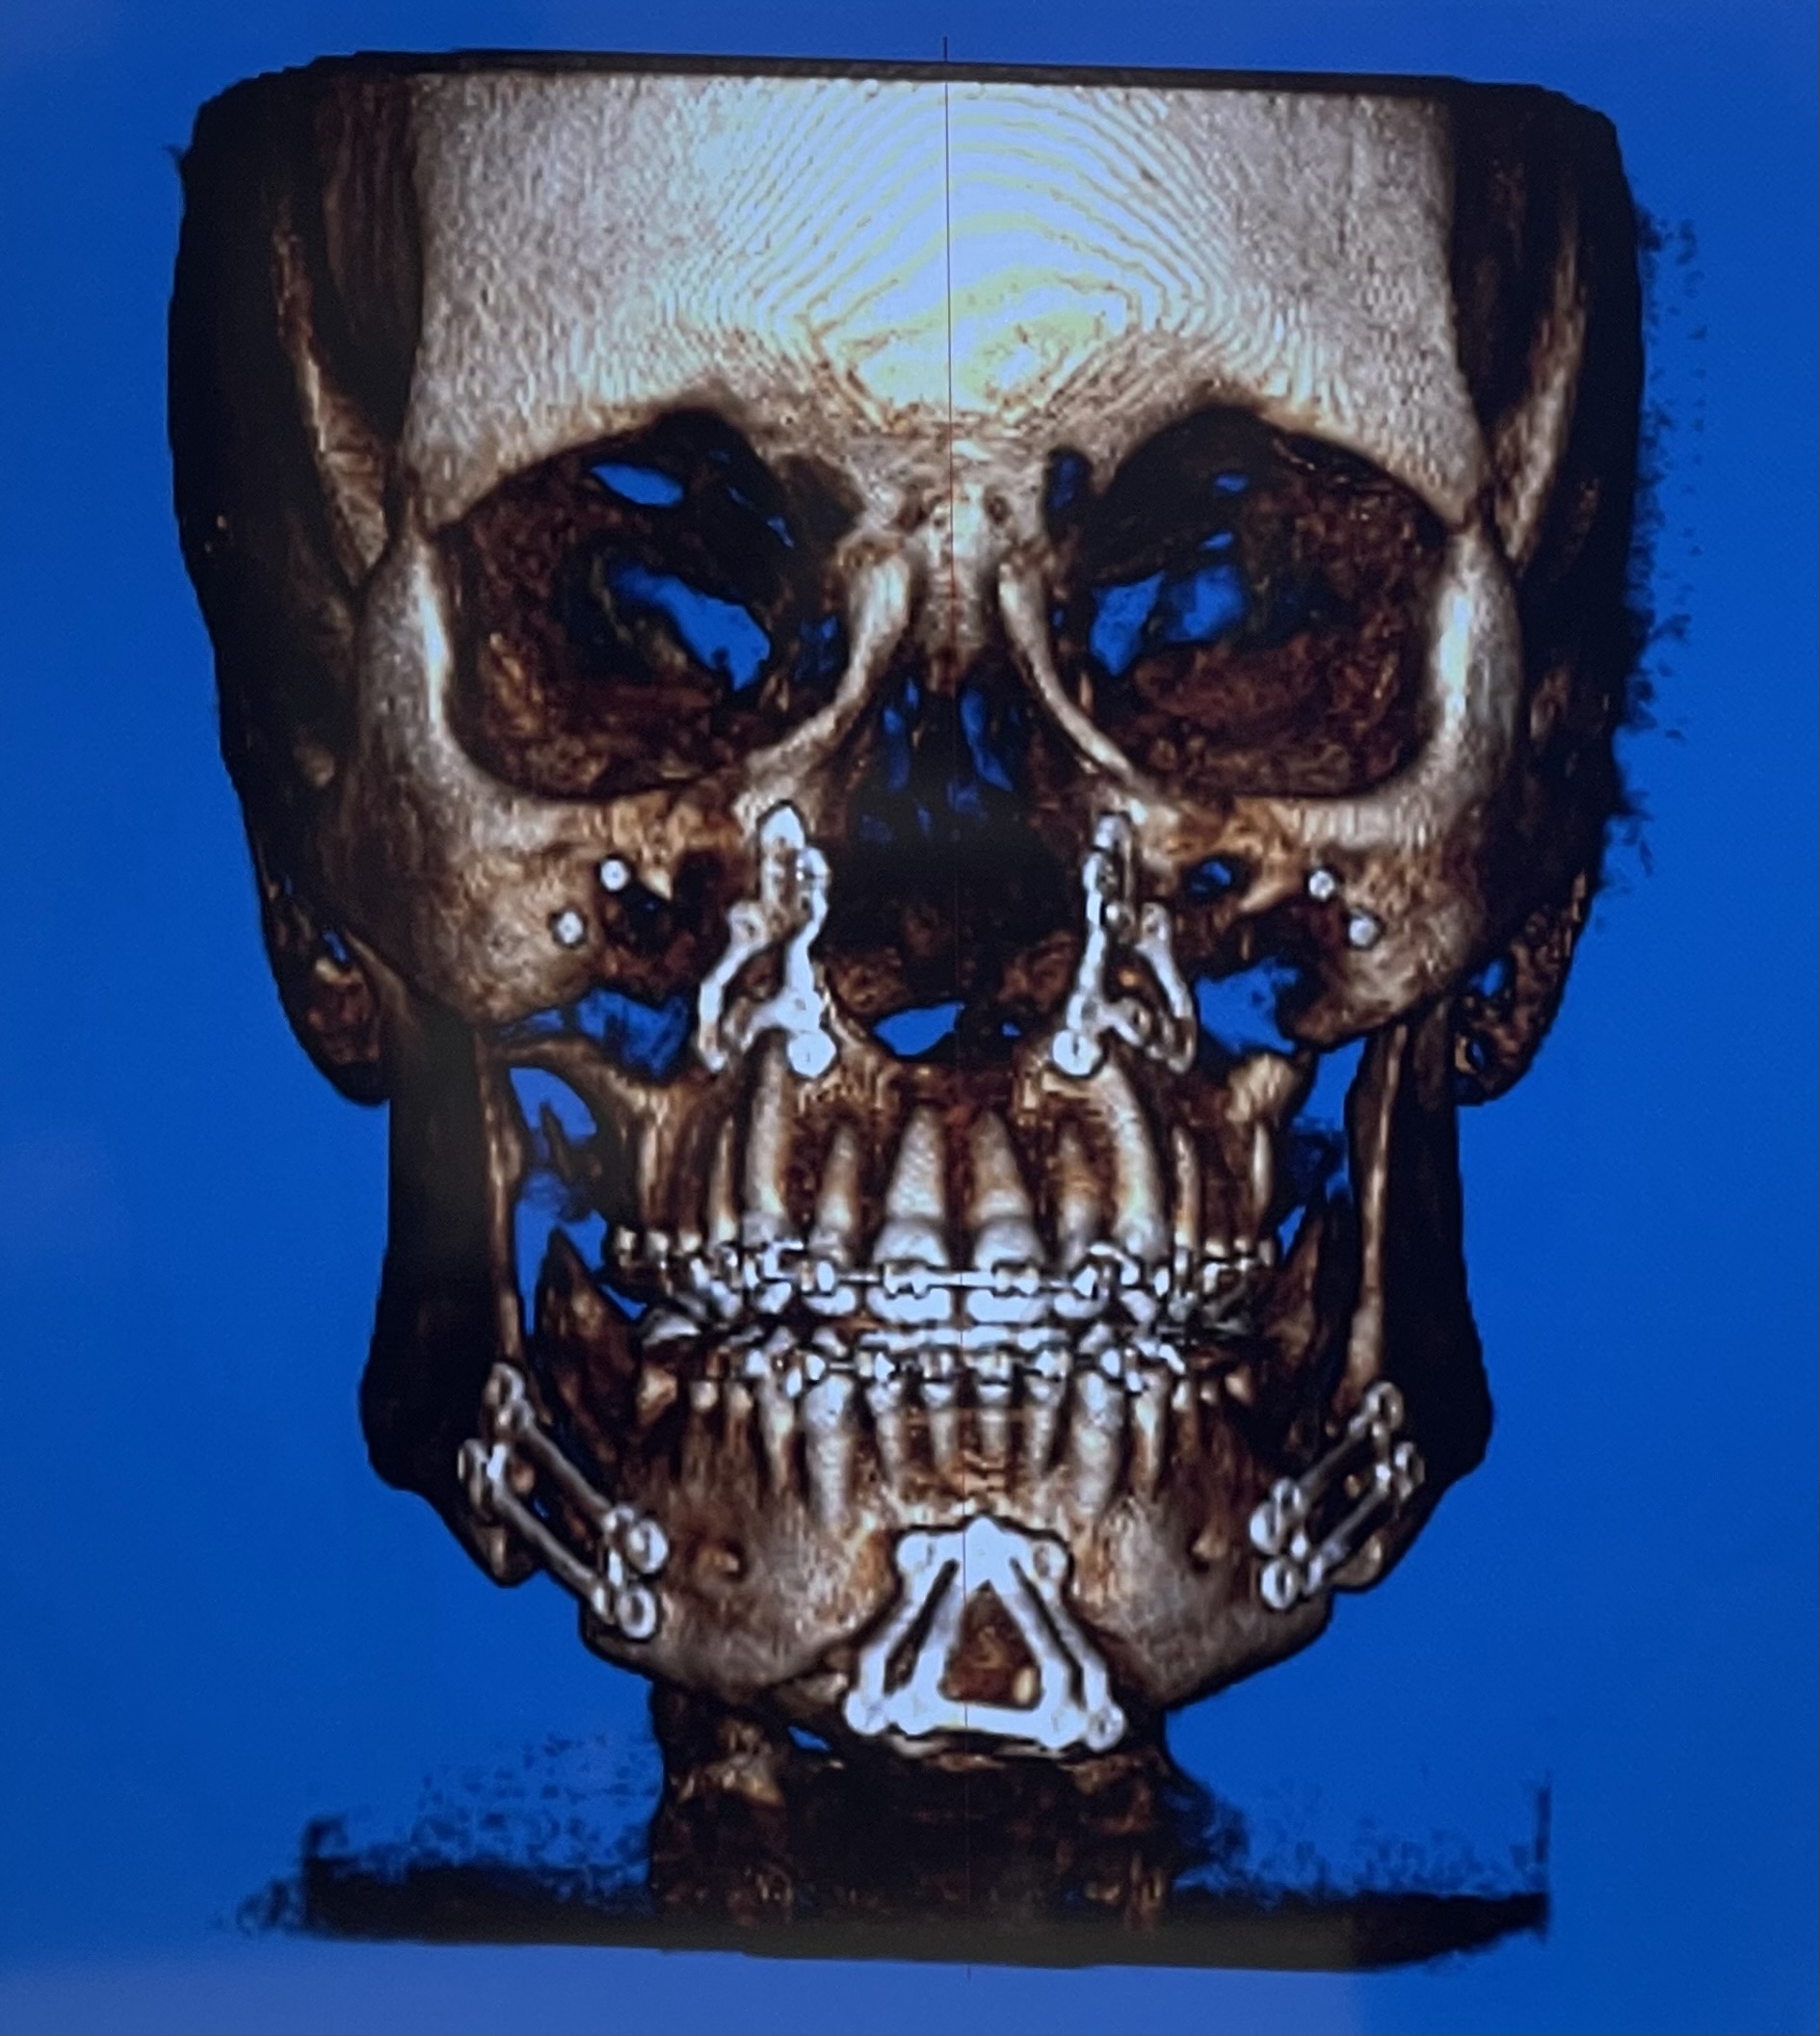

16mm genio-only projection with jawline implants. Clearly a trimax case, but for some bizarre reason, Ramieri chose to only do a genio instead. Note the deep mentolabial fold and the bunching around the submental from the transition between the chin and the rest of the mandible.

Case #2

Chin reduction and rotation to address asymmetry.

Look at the transition between the chin and the mandible; clearly a step-off. Is this because of chin shaving/reduction having the opposite of a tightening effect, or just simply poor technique on Ramieri's part?

Now I DM'd a user who claims he has spoken to 5 people who got genio with Ramieri, and all of them had a combo or at least an issue with asymmetry and step-off, even with conservative movements.

Genio is supposed to be a relatively simple surgery, and hard to mess up. Is it really just poorly planned cuts or something else about the technique? Or is the step-off exaggerated in these after photos because of soft tissue swelling? Is the problem case-specific, or is Ramieri generally bad at genioplasties? I don't think it's fair to judge based on 2 cases and a few supposed forum anecdotes, but it doesn't set a good precedent for sure.